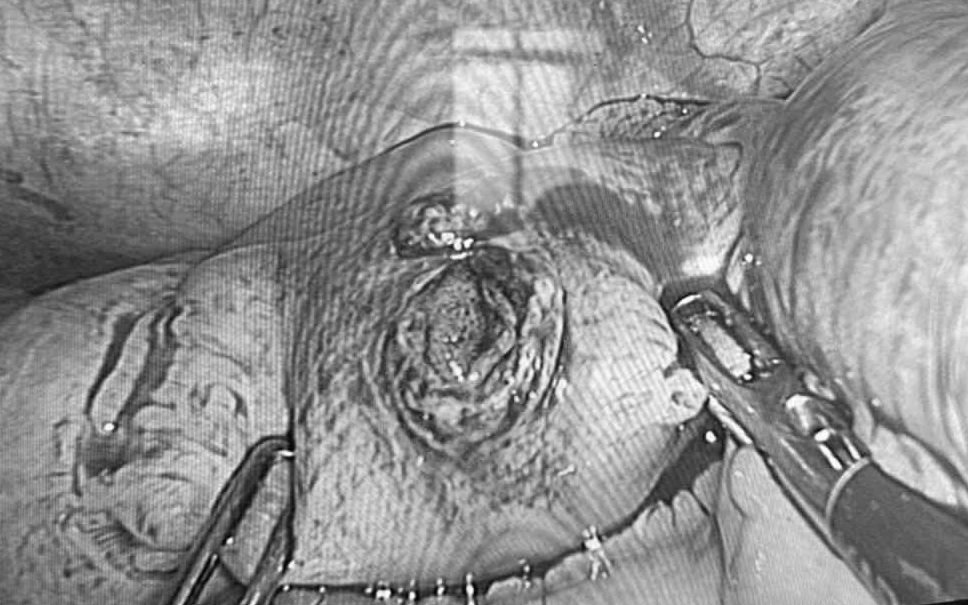

Ngay lập tức, ê-kíp phẫu thuật thuộc Khoa Ngoại Tiêu hóa – Bệnh viện Kiến An đã tiến hành mổ cấp cứu khẩn cấp. Trong quá trình can thiệp, các bác sĩ đã tập trung xử lý các tổn thương phức tạp; cầm máu và tạo hình lại mạc treo ruột; cắt bỏ 2 đoạn hỗng – hồi tràng đã bị dập nát, tổn thương nặng không thể bảo tồn và khâu phục hồi nhiều lỗ thủng trên ruột non.

Nhờ sự phối hợp nhịp nhàng giữa các chuyên khoa Phẫu thuật và Gây mê hồi sức, ca mổ đã diễn ra thành công, kiểm soát hoàn toàn các nguồn chảy máu và tình trạng nhiễm trùng ổ bụng.